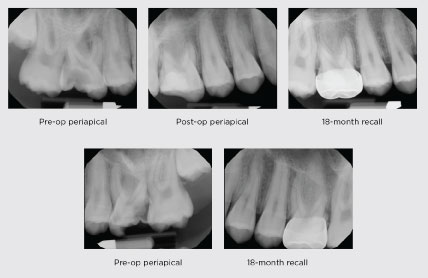

Figure 2 – Indirect pulp therapy

A 7-year-old male presented with multiple carious lesions on primary and permanent teeth. Of note, two lesions presented on permanent mandibular first molars with immature apices. Due to patient cooperation and the extent of dental needs, the patient was treated under general anesthesia. Teeth #19 and #30 received indirect pulp caps and full coverage restorations. Upon 18-month recall apexogenesis is evident. While currently evidence does not favor one material over another, calcium silicates such as SmartMTA deserve attention in the coming years given the sealing potential.

In order to be candidates for indirect or direct pulp therapy, teeth should be free of signs of necrosis and irreversible pulpitis. They should be free of spontaneous pain (or history thereof), respond to sensibility testing, be free of swelling or sinus tracts, and have normal radiographic findings. Abnormal radiographic findings include calcifications in the pulp space, apical pathosis, or a widened periodontal ligament14 (see Figure 2).